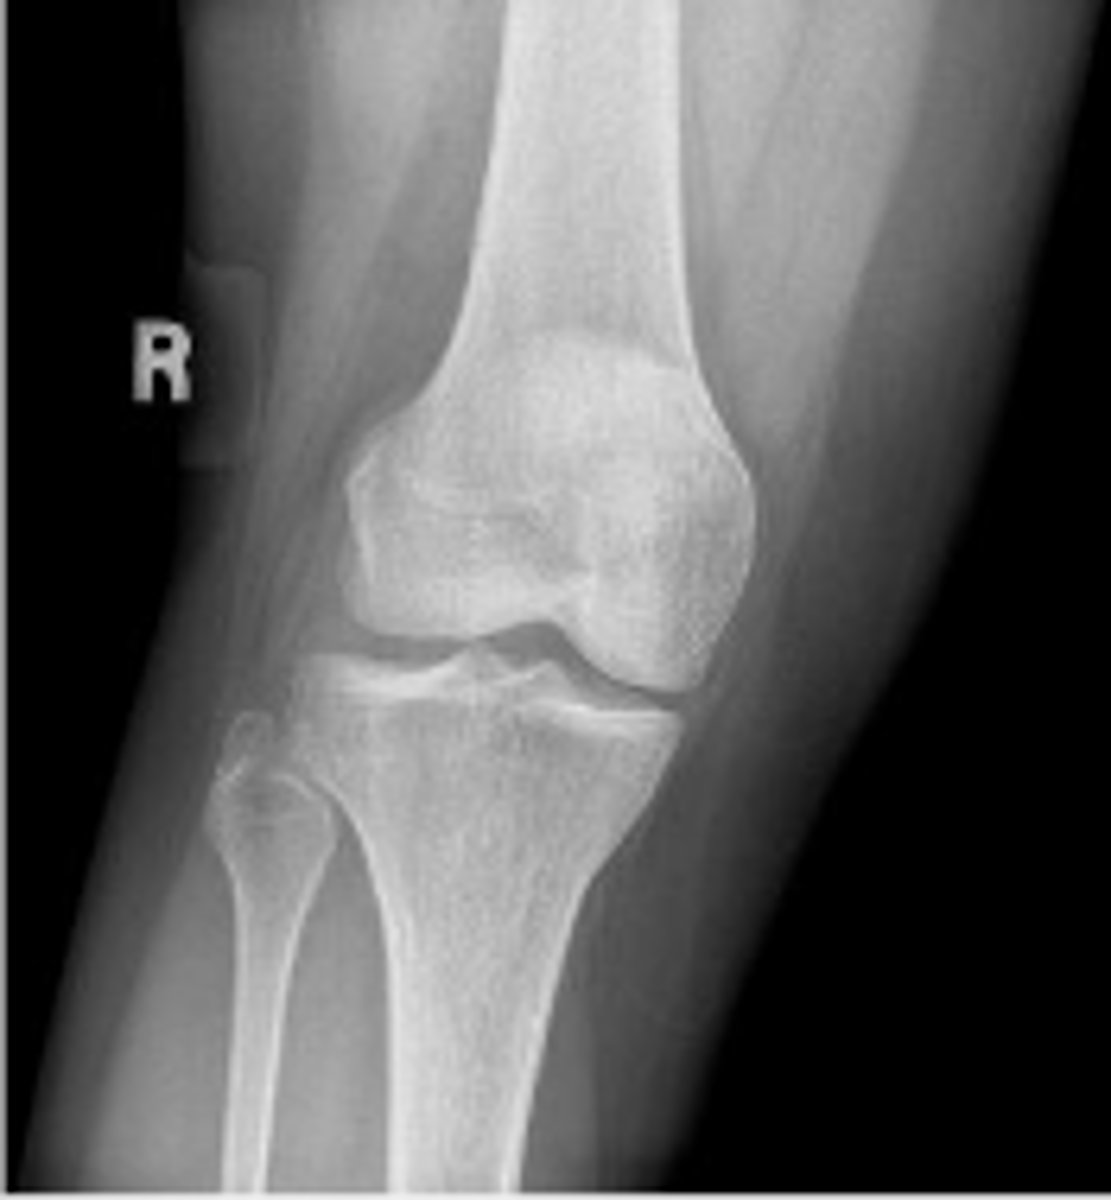

Right internal oblique knee

What is the name of the radiographic view?